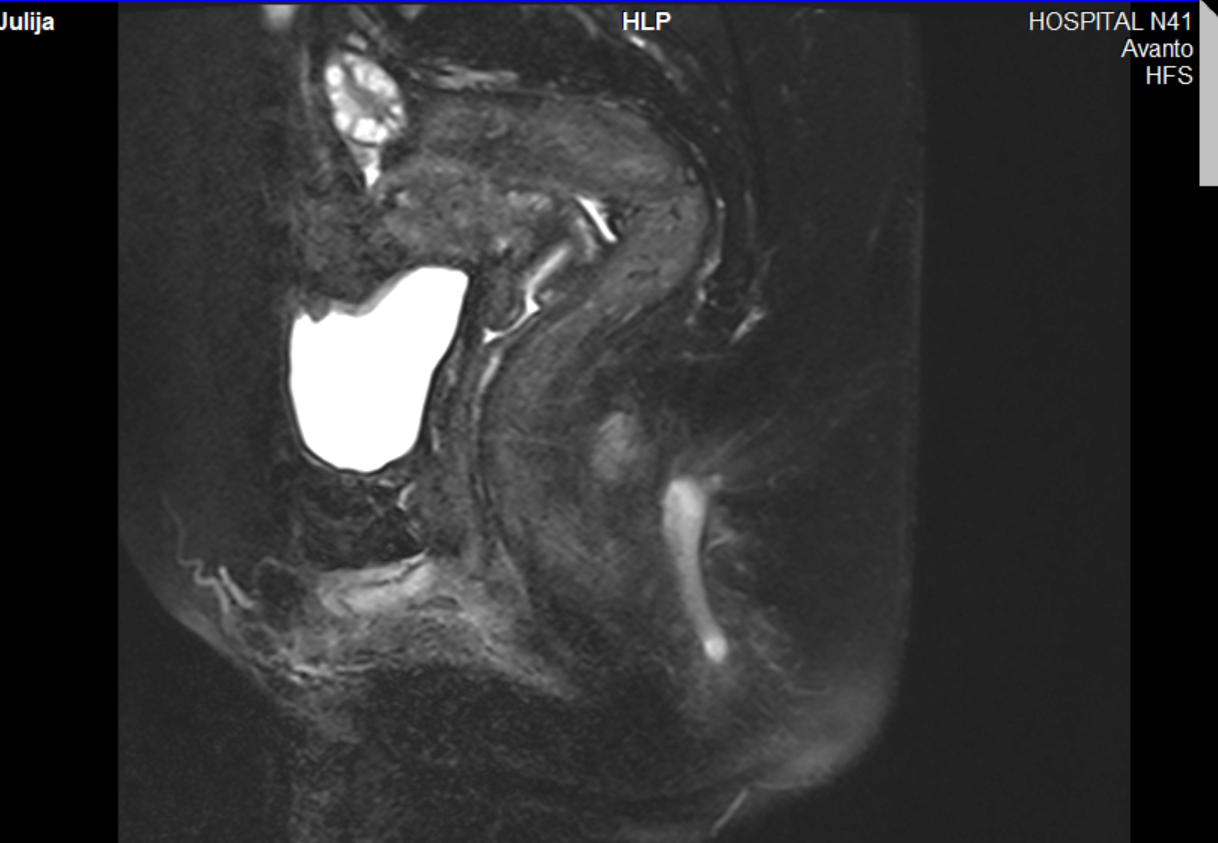

Сделала МРТ - а там капец

Мало того, это сложный случай и в платной клинике мне в малоинвазивных операциях отказали. А в бесплатную мне теперь идти страшно. В Екб платно такое не оперируют вообще. Буду оперироваться в платной в МСК в 2 этапа и это все растянется на полгода если все будет успешно.